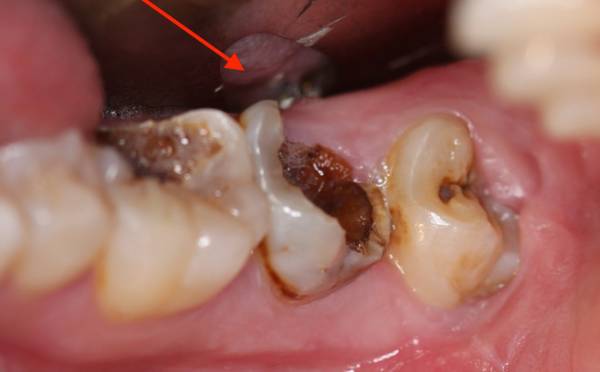

ảnh minh họa

Một trong những căn bệnh liên quan đến răng miệng quen thuộc tưởng chừng như đơn giản nhưng có thể gây đau đớn tột cùng, thậm chí cả tử vong chính là sâu răng.

Trước hết, sâu răng chính là tình trạng vùng răng hoặc chân răng bị tổn thương, gây ra đau đớn. Có rất nhiều nguyên nhân dẫn đến răng bị sâu và điều đó sẽ ngày càng trở thành một mối đe dọa rất lớn nếu như không được kiểm soát kịp thời.

Khi chúng ta ăn uống, những mẩu thức ăn dư thừa sẽ trở thành mảng bám trên răng, lên men vi khuẩn và tiết ra axit phá hủy men răng (lớp men cứng phủ ngoài bề mặt răng).

Nếu không được vệ sinh răng sạch sẽ, sau một thời gian, vi khuẩn sẽ phá vỡ lớp men răng, tạo ra một vùng khiến cho vi khuẩn dễ dàng thâm nhập gây tổn thương răng. Như vậy, đây chính là nguyên nhân dẫn đến sâu răng và viêm nướu.